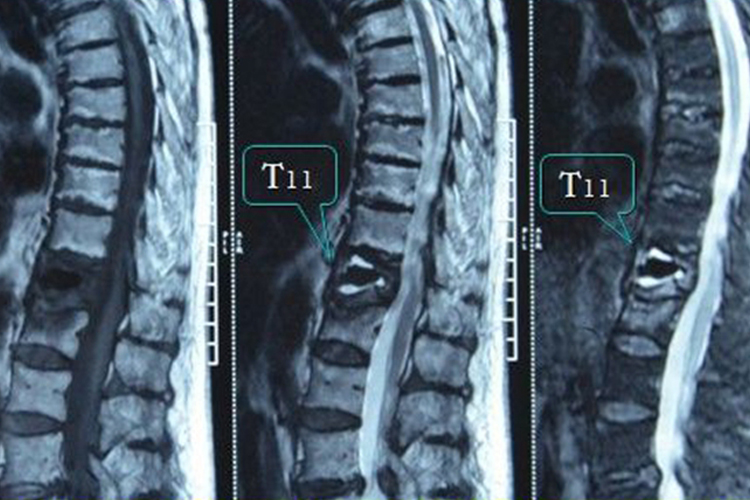

椎体11,12骨折指胸椎第11-12节骨折,患者可出现局部疼痛、站立及翻身困难等症状。

胸椎第11-12节骨折患者主要症状为局部疼痛,站立及翻身困难。腹膜后血肿刺激腹腔神经节,会使肠蠕动减慢,常出现腹痛、腹胀甚至肠麻痹症状。患者也可能合并出现脊髓神经损伤症状,表现为下肢的感觉及运动、反射异常。

胸椎第11-12节骨折对于稳定性骨折且不伴有神经症状的患者,可以进行保守治疗。保守治疗包括卧床、悬吊牵引和姿势复位等,伤后4-8周可戴支具下地活动,需要定期拍片复查。

当原始X线片显示前柱的压缩大于50%或伴有后柱的损伤时,为不稳定骨折。如果患者神经系统检查正常,可遵医嘱采取脊柱后路内固定融合术。骨折脱位需给予复位和内固定,以恢复脊柱的稳定性。